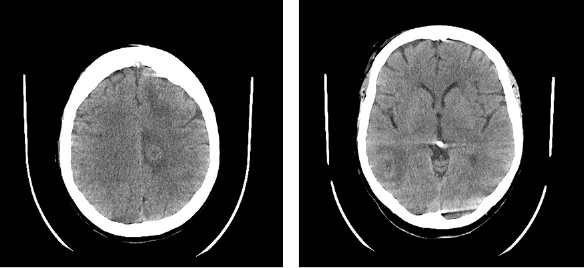

In November 2023, a 55-year-old female patient was hospitalized following a fall at home which resulted in a left elbow fracture. The patient had been feeling dizzy before the incident, prompting a head CT to exclude a head trauma and determine the cause of the dizziness. The CT revealed multiple brain lesions, with differential diagnoses including metastases and abscesses (Fig. 1), necessitating further evaluation via magnetic resonance imaging (MRI). The patient’s medical history indicates that she had been diagnosed with seropositive myasthenia gravis in July 2015. The diagnosis was confirmed by the presence of positive antibodies against acetylcholine receptors (AChR), and a muscle biopsy was performed. The patient was taking Mestinon 60mg x 3, Prednisolone 5mg x 1, and Azathioprine 50mg x 2 for treatment. Plasmapheresis was used to treat exacerbations of myasthenia gravis.